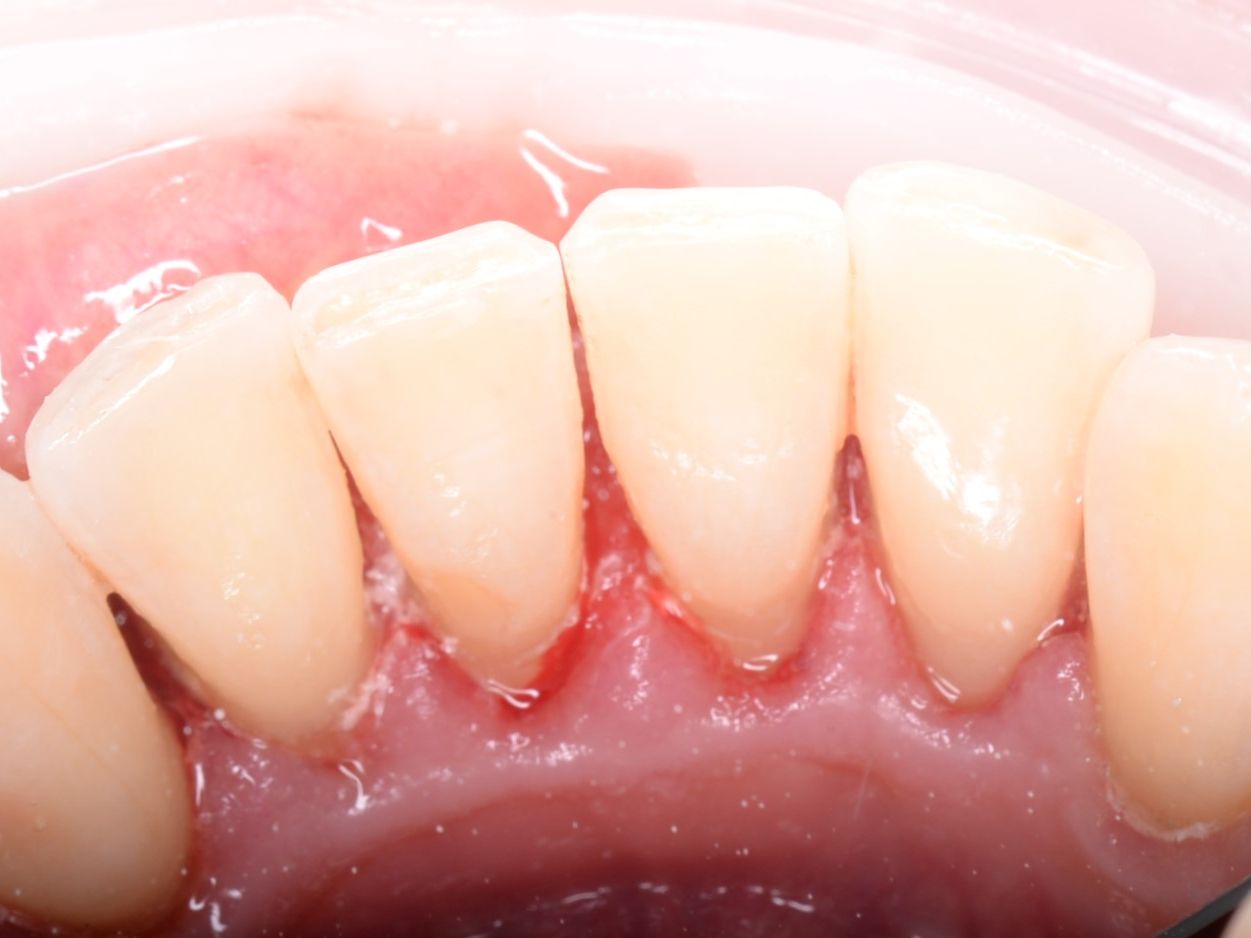

• Профессиональной гигиеной полости рта, включая снятие зубного камня и пигментированного налёта с использованием современного оборудования.